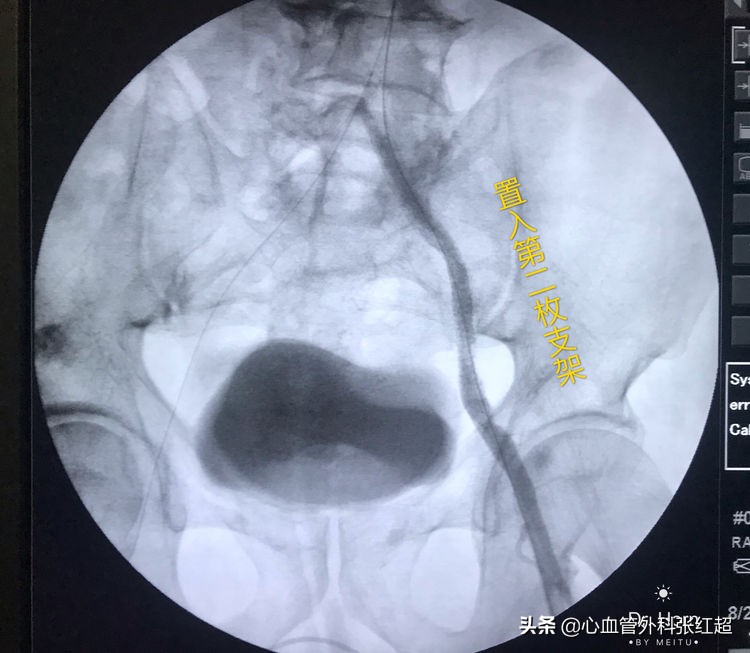

放两枚支架更容易保证远端释放到位

术后足背、胫后动脉搏动均恢复。